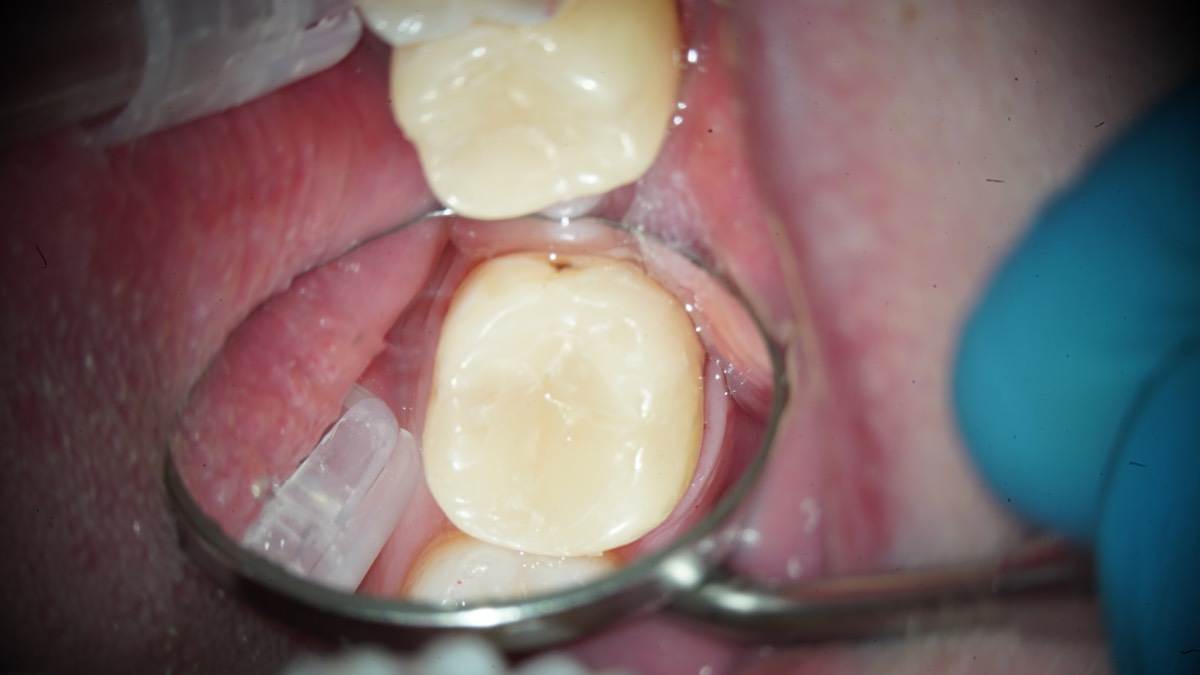

Гарриевич Опубликовано 10 часов назад Автор Поделиться Опубликовано 10 часов назад Еще один осмотр спустя 3 года и полное заживление 1 Ссылка на комментарий